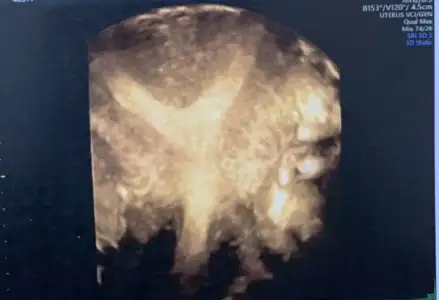

Amin canım Rabbim herkese hakkıyla annelik babalık nasip etsin inşallah. Bende önümüzdeki hafta Ankara’da Bülent zeyneloğlu nda rahim düzeltme ameliyatı olacağım. Benim hsg sonucu sağ tüpüm tıkalı sol hafif açık gibi çıktı ama Bülent hoca hsg nin çok kötü çekildiğini, histereskopi ile birlikte laparoskopi de yaparak tüplerin ne durumda olduğunu görmek istediğini söyledi. Eğer tüplerimde sorun varsa direk tüp bebeğe geçeceğiz zaten ama o süreci hiç yaşanmadan kendiliğinden olmasını çok istiyorum. Sen iki kere histereskopi olduğuna göre gayet kolay bir operasyon diye tahmin ediyorum ancak Bülent hoca benim için rahim çok aşırı y o yüzden tek operasyonla düzenlmeyebilir dedi. Umarım tek operasyonla hallolur tüplerimdede sorun yoktur hemen ertesi ay hamile kalırım. Hepsinin aynı anda olma ihtimali çok az ama Rabbim ol derse olur ne yapalım. Benim rahmim de bu şekilde bu arada

Amin canım Rabbim herkese hakkıyla annelik babalık nasip etsin inşallah. Bende önümüzdeki hafta Ankara’da Bülent zeyneloğlu nda rahim düzeltme ameliyatı olacağım. Benim hsg sonucu sağ tüpüm tıkalı sol hafif açık gibi çıktı ama Bülent hoca hsg nin çok kötü çekildiğini, histereskopi ile birlikte laparoskopi de yaparak tüplerin ne durumda olduğunu görmek istediğini söyledi. Eğer tüplerimde sorun varsa direk tüp bebeğe geçeceğiz zaten ama o süreci hiç yaşanmadan kendiliğinden olmasını çok istiyorum. Sen iki kere histereskopi olduğuna göre gayet kolay bir operasyon diye tahmin ediyorum ancak Bülent hoca benim için rahim çok aşırı y o yüzden tek operasyonla düzenlmeyebilir dedi. Umarım tek operasyonla hallolur tüplerimdede sorun yoktur hemen ertesi ay hamile kalırım. Hepsinin aynı anda olma ihtimali çok az ama Rabbim ol derse olur ne yapalım. Benim rahmim de bu şekilde bu arada.